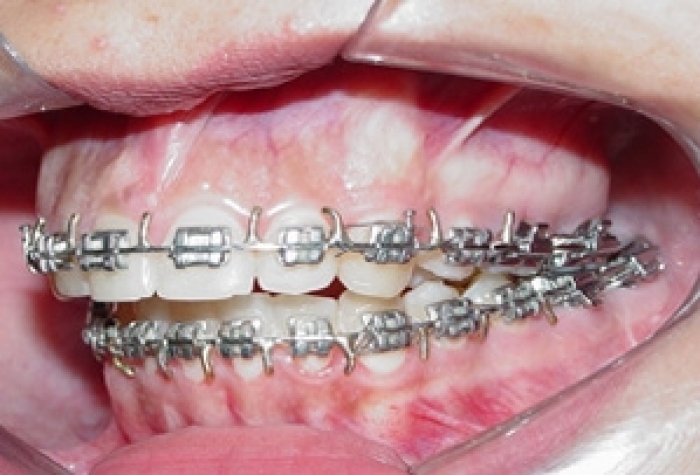

Mordida inicial

Mordida após a remoção do aparelho